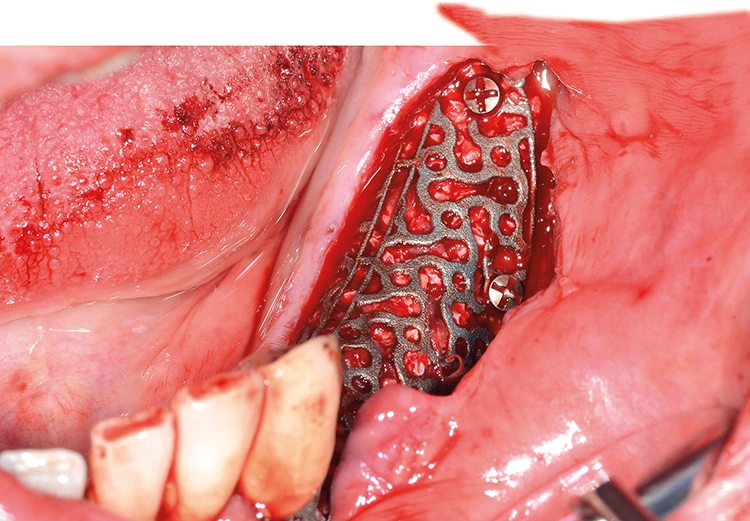

Präoperativ wurde im Sinne eines Backward Planning erst die spätere Implantatposition und in Kenntnis dieser, die Ausdehnung des Titangitters festgelegt. Hierbei wurde festgestellt, dass sich zum einen das Foramen mentale direkt im Augmentations- und Implantationsbereich befindet und zum anderen der Verlauf des Nervus alveolaris inferior, trotz Augmentation, nur relativ kurze Implantate zulassen wird.

Bei der digitalen Planung des Gitters wurde dieser Aspekt besonders berücksichtigt und zudem auf die Lage des Foramen mentale speziell geachtet. Das Gitter wurde im Austrittsbereich ausgespart, um eine Traumatisierung zu vermeiden (Abb. 4-19).